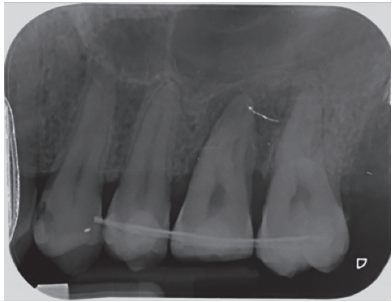

In the radiograph examination, through a panoramic radiograph, both lower third molars were seen retained in horizontal position (Figure 3), and apical radiolucent images in positions of 2.6 and 4.6. The cone beam scan evaluated the root morphology of the left upper third molar and the size of the apical radiolucent lesion of the left upper first molar (Figure 4), necessary data to assess the degree of adaptation of the donor tooth in the recipient bed.

associated with the root remains of 2.6 and the conical root of 2.8 are seen.

After reducing the occlusion, a cross stitch with monofilament suture (AragoTM, Barcelona, Spain) was applied around the transplanted tooth to increase its fixation (Figure 13), performing an intraoperative periapical radiograph with parallelism technique (Figure 14).

The published clinical studies evaluate patients clinically and radiographically, by periapical radiographs9,10,12,15,17,18 or by periapical and panoramic radiographs4,13,14. The periapical radiography shows the presence of radiolucent areas, external and internal root resorptions, ankylosis and the state of root development18, being fundamental in the evolution of this therapeutic modality. In the present clinical case, a radiolucent area around the tooth was radiographically visible, which was modified over time, to achieve a similar bone density of the bone in contact with the transplanted tooth, compared to the surrounding bone. Additionally, no apical lesions or root resorption were observed during the followup period.